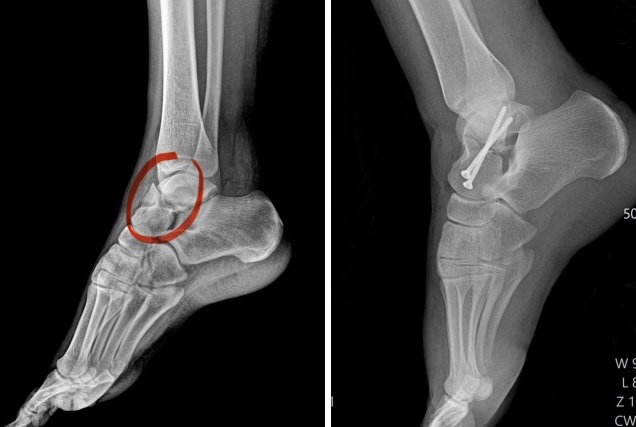

Воронежские врачи спасли 22-летнюю девушку с редким переломом, который она получила после падения с лошади. Как сообщили в облздраве, горожанка поступила в больницу в начале апреля. Медики выявили сложную травму - закрытый перелом левой таранной кости со смещением костных отломков. Специалисты решили провести операцию. Травматологи-ортопеды Олег Ипполитов и Евгений Козюбенко сопоставили отломки кости и зафиксировали их винтами под артроскопическим контролем. Это прибор, соединённый с камерой и осветителем, который вводят в полость сустава через небольшие проколы в теле. Преимущество такой операции - малоинвазивность и малотравматичность. Врачи смогли достичь полного анатомического сопоставления костных отломков. Пациентку выписали из стационара в удовлетворительном состоянии спустя четыре дня после операции. Александра ГАНИНА

Фото: пресс-служба облздрава